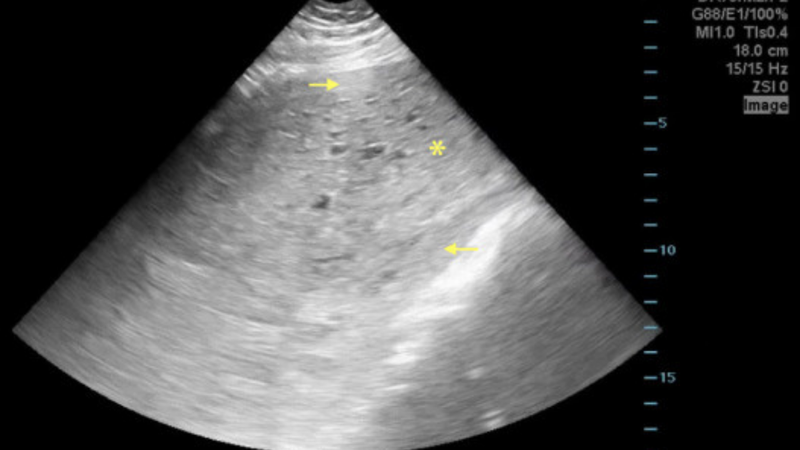

Ung thư nhau thai được chẩn đoán qua các xét nghiệm và phương pháp hình ảnh học nhằm phát hiện khối u và đánh giá mức độ lan rộng. Đầu tiên, bác sĩ tiến hành khám vùng chậu và thể chất để tìm dấu hiệu bất thường. Xét nghiệm máu, đặc biệt là xét nghiệm hCG, giúp xác định mức độ hormone cao bất thường, một dấu hiệu của ung thư nhau thai. Các phương pháp hình ảnh như siêu âm, CT, MRI, và X-quang ngực được sử dụng để phát hiện vị trí và mức độ lan của ung thư. Bệnh nhân cũng cần được theo dõi thường xuyên, đặc biệt sau các thai kỳ nguy cơ cao.